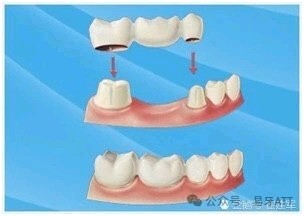

与固定牙相比:无需磨削邻牙,为独立个体,不影响邻牙生物性能。